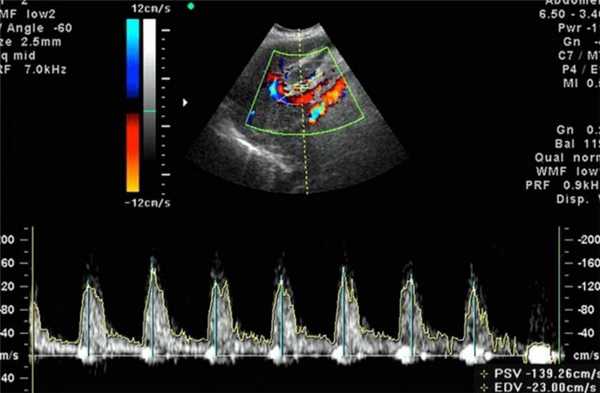

Во время беременности доплерография может использоваться для оценки кровотока в матке матери или, чаще, кровообращения у плода. Ток крови в артериях имеет иной внешний вид, чем в венах. Венозный отток в основном равномерный, без изменений во время сердечного цикла, если только у плода нет неблагоприятной клинической ситуации, такой как ограничение внутриутробного развития.

Артериальный кровоток совсем другой. Независимо от оцениваемой артерии скорость крови, проходящей через артерию, будет изменяться в течение каждого сердечного цикла. Она будет максимальной, когда сердце первоначально выталкивает кровь из левого желудочка в период систолы. Затем желудочек снова начинает заполняться, что называется диастолой. На экране врач видит графики, которые сравнивает с нормативами, делая заключение после процедуры УЗИ.

- Цветная допплерография. Изображение текущей крови представлено красным или синим цветом в зависимости от направления кровотока и его скорости.

Для обследования используется такой же ультразвук, как и при обыкновенном ультразвуковом исследовании. Отличие заключается в особом датчике, работающем на основе допплеровского эффекта, и интерпретации полученных данных. При исследовании фиксируются ультразвуковые волны, отраженные не от статичных тканей, а от подвижных объектов - клеток крови, в результате чего частота отраженных лучей сильно изменяется в сравнении с изучаемыми. Аппарат обрабатывает полученные данные и создает двухмерное цветное изображение. Благодаря этому возможно оценить скорость и направление кровотока, анатомию и проходимость сосудов.